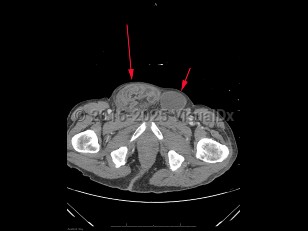

diflucortolone, 50-59 year old Female

231 Diagnoses match 0 of 1 findings